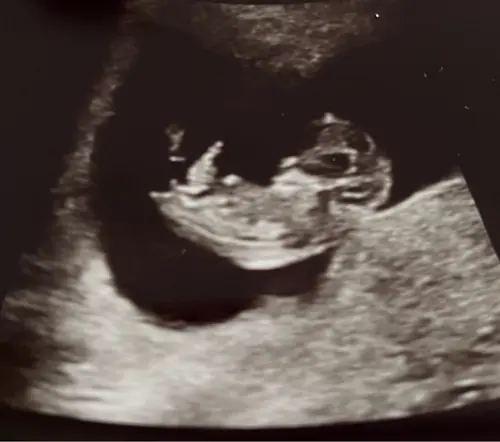

13 weken en 1 dag, ben heel erg benieuwd of jullie al iets kunnen zien😊

5 maanden geleden

Reactie op ashleyjoy

Hi termijn? Als het voorbij 12 is denk ik een jongennn.